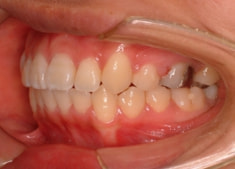

上顎前突+右下7番重度埋伏

(右下7番目の永久歯が下顎の中に埋まったまま、親知らずが上に乗っている)

治療前